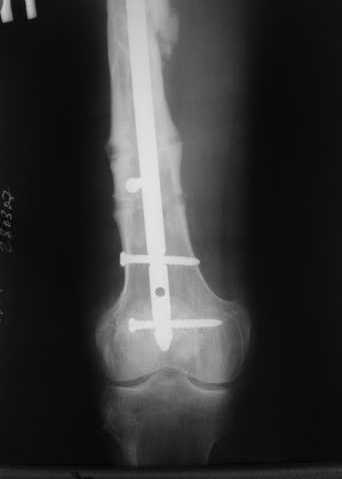

Пациенту М., 30-ти лет, 1,5 года назад в одной из московских больниц был выполнен остеосинтез бедренной кости штифтом UFN (диаметр штифта 9 мм).

К нам больной поступил с признаками ложного сустава бедренной кости, перелома

штифта и дистального блокирующего винта (images 1,2,3).

27 марта выполнено удаление блокирующих винтов (сломанный винт пришлось высверливать цапфен-бором), сломанного штифта (дистальный фрагмент удален через канал, образованный разверткой из коленного сустава - image 4),

рассверливание костно-мозгового канала, реостеосинтез штифтом UFN (при проведении штифта в дистальном отломке мы использовали поляризующий винт, диаметр штифта 10 мм). После операции в связи гемартрозом дважды (на 1 и 3 сутки) выполняли пункцию коленного сустава. Сейчас признаков скопления жидкости в полости сустава нет. Послеоперационные рентгенограммы - images 5, 6, 7.